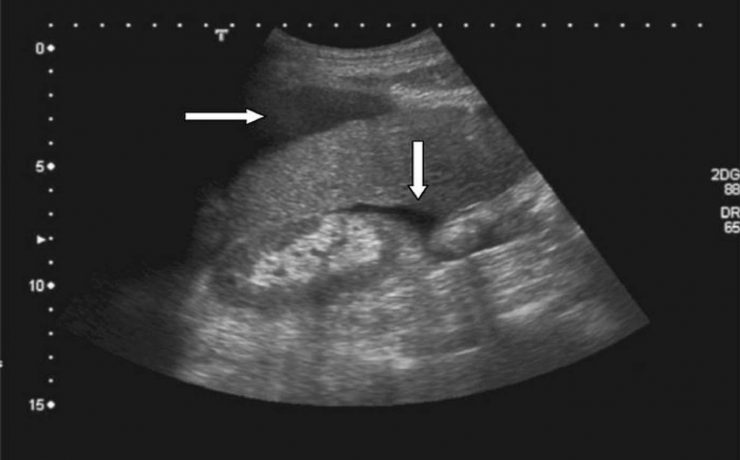

ÚTERO Y OVARIOS Al estudiar el hueco pélvico hay que tener en cuenta la anatomía del sistema reproductor femenino ya que partiendo de esto se podrán identificar anomalías en los mismos. Un punto importante para el estudio del hueco pélvico es utilizar la vejiga urinaria como ventana sónica, sin caer